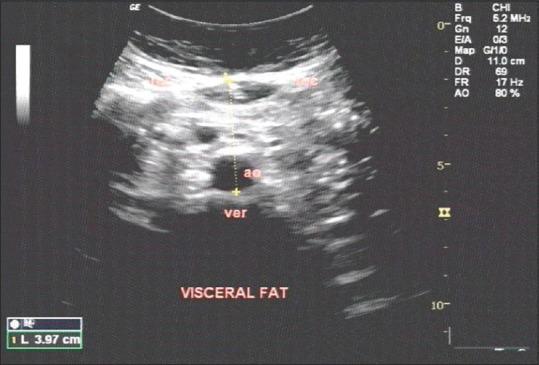

Forty obese and forty nonobese volunteers of both genders were recruited. Parameters such as body mass index (BMI), waist circumference (WC), and blood pressure were evaluated. Fasting blood sugar (FBS), fasting insulin level, hemoglobin A1c (HbA1C), lipid profile, TNF-α, IL-6, hs-CRP, and AN levels were measured. IR was evaluated by homeostatic model assessment-IR method. Abdominal adiposity was measured by ultrasonography. The results were statistically evaluated by appropriate tests.

BMI, WC, and visceral fat were high in the obese group. Females had higher subcutaneous fat in both groups. HbA1C was marginally high in the obese group (P = 0.014). IR was high in all the groups, obese males showing higher values (not significant[NS]). Total cholesterol and low-density lipoprotein were high in the obese group (P = 0.028, P = 0.003). TNF-α was high in obese males (NS), IL-6 was high in both groups, higher in nonobese females (NS), hs-CRP was high in both groups, higher in females of both groups (NS). AN was high in females of both groups (P = 0.002).

招募了40名肥胖和40名非肥胖的男女志愿者。评估了体重指数(BMI)、腰围(WC)和血压等参数。测量了空腹血糖(FBS)、空腹胰岛素水平、糖化血红蛋白(HbA1C)、血脂谱、TNF-α、IL-6、hs-CRP和AN水平。通过稳态模型评估-IR方法评估IR。通过超声测量腹部肥胖。结果通过适当的测试进行统计学评估。

肥胖组的BMI、WC和内脏脂肪较高。两组女性的皮下脂肪均较高。肥胖组的HbA1C略高(P = 0.014)。所有组的IR均较高,肥胖男性的值更高(无显著性差异[NS])。肥胖组的总胆固醇和低密度脂蛋白较高(P = 0.028,P = 0.003)。肥胖男性的TNF-α较高(无显著性差异),两组的IL-6均较高,非肥胖女性更高(无显著性差异),两组的hs-CRP均较高,两组女性更高(无显著性差异)。两组女性的AN均较高(P = 0.002)。